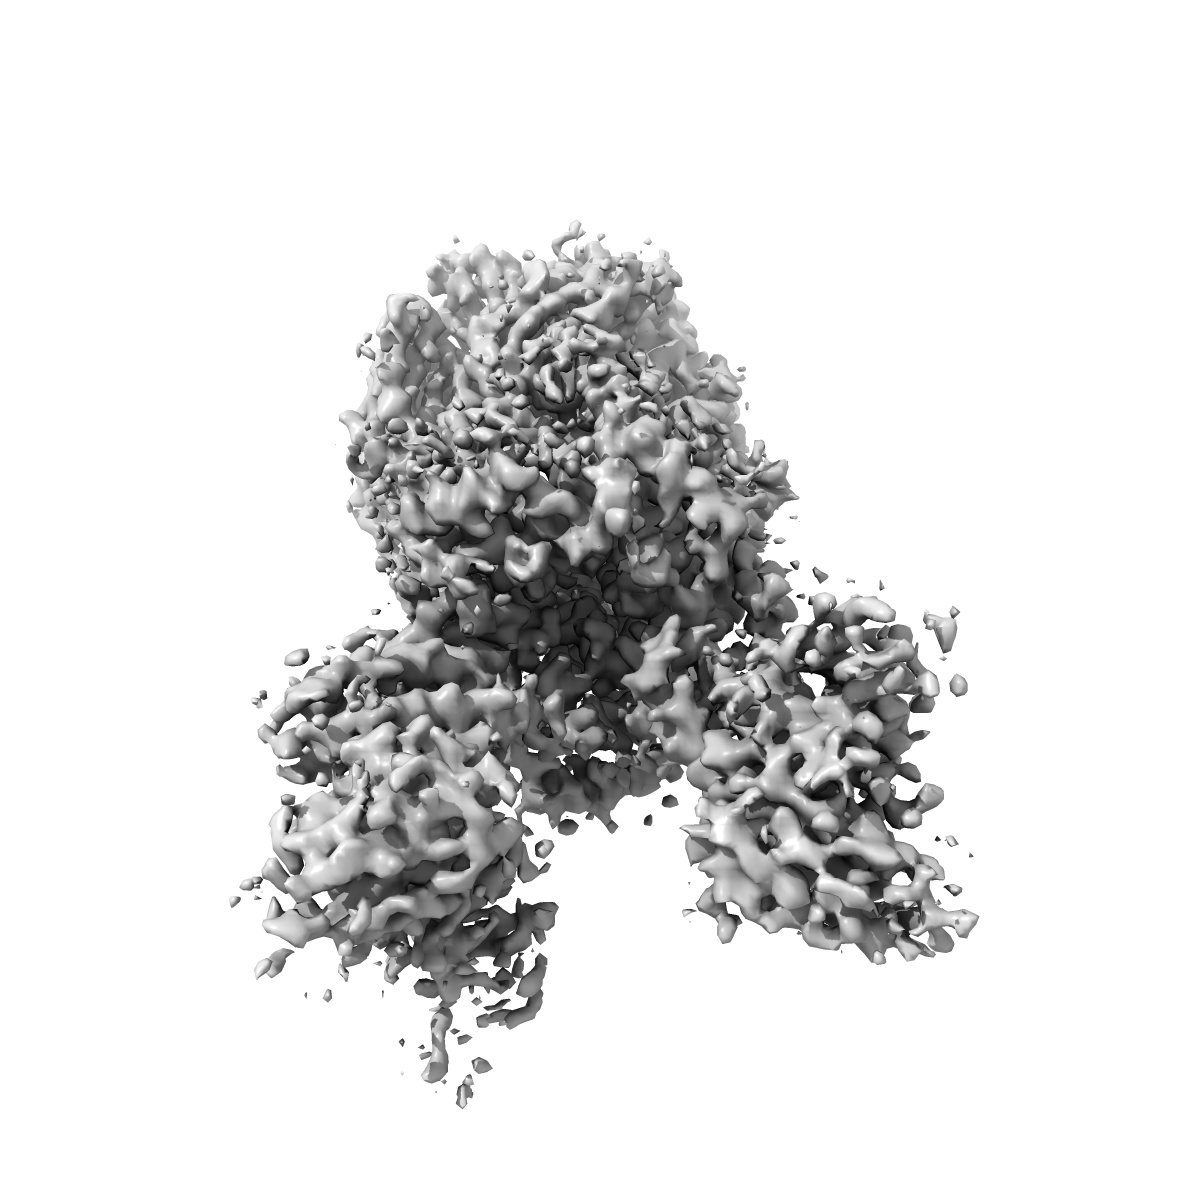

CryoEM structure of human alpha4beta2 nicotinic acetylcholine receptor with varenicline in complex with anti-BRIL synthetic antibody BAK5

Single-particle

3.87 Å

Sample: human alpha4beta2 nicotinic acetylcholine receptor in complex fab fragments and bound to varenicline

Fitted models: 6usf

Synthetic antibodies against BRIL as universal fiducial marks for single-particle cryoEM structure determination of membrane proteins.